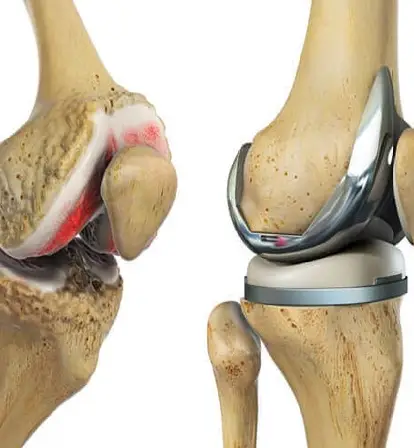

Total knee replacement involves removing damaged joint surfaces and replacing them with artificial components to relieve pain, restore function, and improve overall quality of life. It is commonly recommended for patients with severe arthritis, degenerative joint disease, or injuries that limit mobility and daily activities.

Modern TKR surgery incorporates advanced technology, including robotic assistance, to enhance precision and improve the alignment of implants. This ensures better long-term outcomes, helping patients regain strength, flexibility, and confidence in their knees after surgery.

TKR surgery involves removing the damaged knee joint surfaces and replacing them with artificial implants that mimic natural movement. Robotic assistance may be used for precise implant alignment, enhancing joint stability and function.